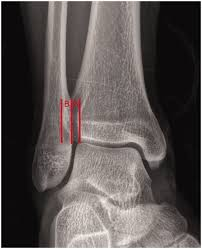

AP ankle structures best demonstrated

Medial mortise joint open.

Lateral mortise closed.

Some superimposition of distal fibula with tibia and talus.

Mortise ankle positioning/factors:

15-20 degrees internally rotated or until intermalleolar line appears parallel to IR

Mortise ankle structures best demonstrated

Ankle mortise joint space open between medial and lateral malleoli.

Minimal superimposition at the distal tibiofibular joint.